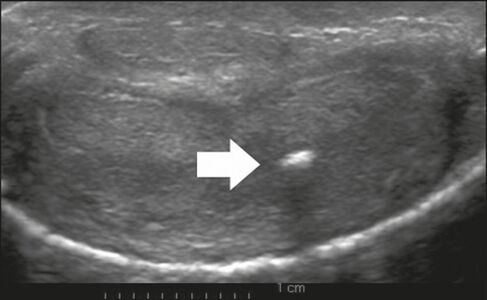

Peyronie's disease is characterized by fibrotic thickening of the tunica albuginea, which can lead to curvature of the penis and difficulty in achieving an erection. Penile fibromatosis (Peyronie's disease) is marked by the formation of fibrous plaques identified as areas where the tunica albuginea is thickened. Although plaques are more common on the dorsum of the penis, they can also be seen on the ventral face, lateral face, or septum.[1]

Figure 6: Transverse ultrasound of the penis, in a ventral view, in the middle portion of the penis. Note the echoic image with posterior acoustic shadowing, corresponding to calcification (arrow), in the left corpus cavernosum.[1]